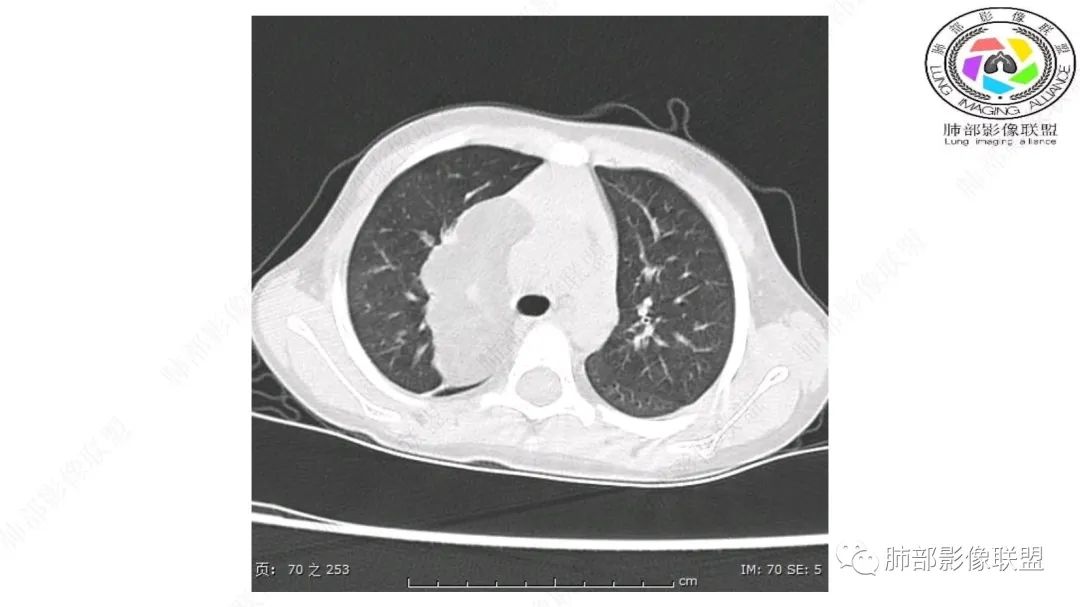

患儿3岁 咳嗽检查发现纵隔占位。右肺上叶受压表现,占位以脂肪组织密度为主,似见分隔,首先考虑为脂肪母细胞瘤,鉴别脂肪瘤,畸胎瘤。

跨肺门,包绕肺血管分支,邻近肺组织受压肺不张。

病灶属于交界区,主体位于肺内,占位效应明显,前方突入胸壁,胸腺受压变形,胸膜显示欠清楚;病灶包绕上叶肺动脉;似乎有体动脉供血。符合肺内的点:包绕上叶肺动脉分支;符合纵隔的点:前方似乎突入胸壁,与胸腺关系比较密切,但是与上腔静脉的关系提示病灶不支持纵隔来源,前纵隔的常规会将上腔静脉受压后移、外移,这是不符合的。

从这个角度符合肺内的,有一点不太踏实的是:似乎突入前胸壁。

1.右上肺-纵隔交界区巨块影,主体位于右肺一侧,紧贴胸腺、头臂干、右锁骨下动脉、上腔静脉、奇静脉等,不能分离,但病灶整体边界清楚。注意上述相邻腔静脉等结构未见受压变形,纵隔亦未见明显向左推移,至少提示两点:

2.肺动脉穿行也许是肺内来源最重要支持点!

脂肪母细胞瘤由成熟程度不同的脂肪组织、纤维间隔、黏液基质、小血管丛等间质成分组成,以脂肪组织与黏液样基质为主,其影像学表现取决于上述组织成分。典型的CT和MRI表现为:前后纵隔均可发生,常见于前纵隔;肿块大小不一,直径多在3cm~7cm,密度均匀,CT值呈水样或脂肪密度,脂肪组织密度或信号为主的肿块,其内密度或信号不均匀,可见粗细不一的分隔影,且有结节、片状影,后者可呈轻中度强化;结节状肿瘤包膜完整;弥漫性者包膜不明显,常呈浸润性生长;周围结构为受压和推移改变,可有少量胸腔积液,淋巴结无增大。